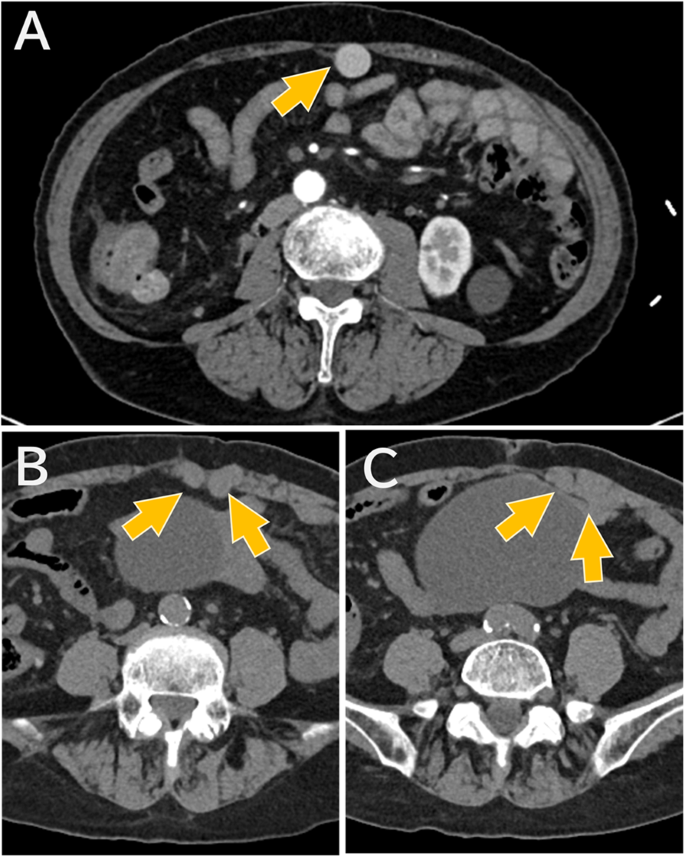

然而,在进行超声引导下的直肌鞘阻滞过程中,发现左侧腹直肌内存在扩张的血管结构(见图1A)。彩色多普勒超声证实了这些结构的血流存在,表明它们是扩张的静脉(见图1B)。因此我们中止了直肌鞘阻滞,转而实施了横向腹横肌平面阻滞。术后对术前CT片的复查显示,腹部壁的静脉在腹直肌内也有扩张(见图2)。

图2

术前CT图像显示腹部壁静脉扩张。(A) 增强CT图像显示腹部壁附近有一条明显的侧支静脉(箭头所示)。(B), (C) 未增强CT图像显示了这条扩张静脉(箭头所示)在腹直肌内的走行路径。※这些切片没有增强CT图像